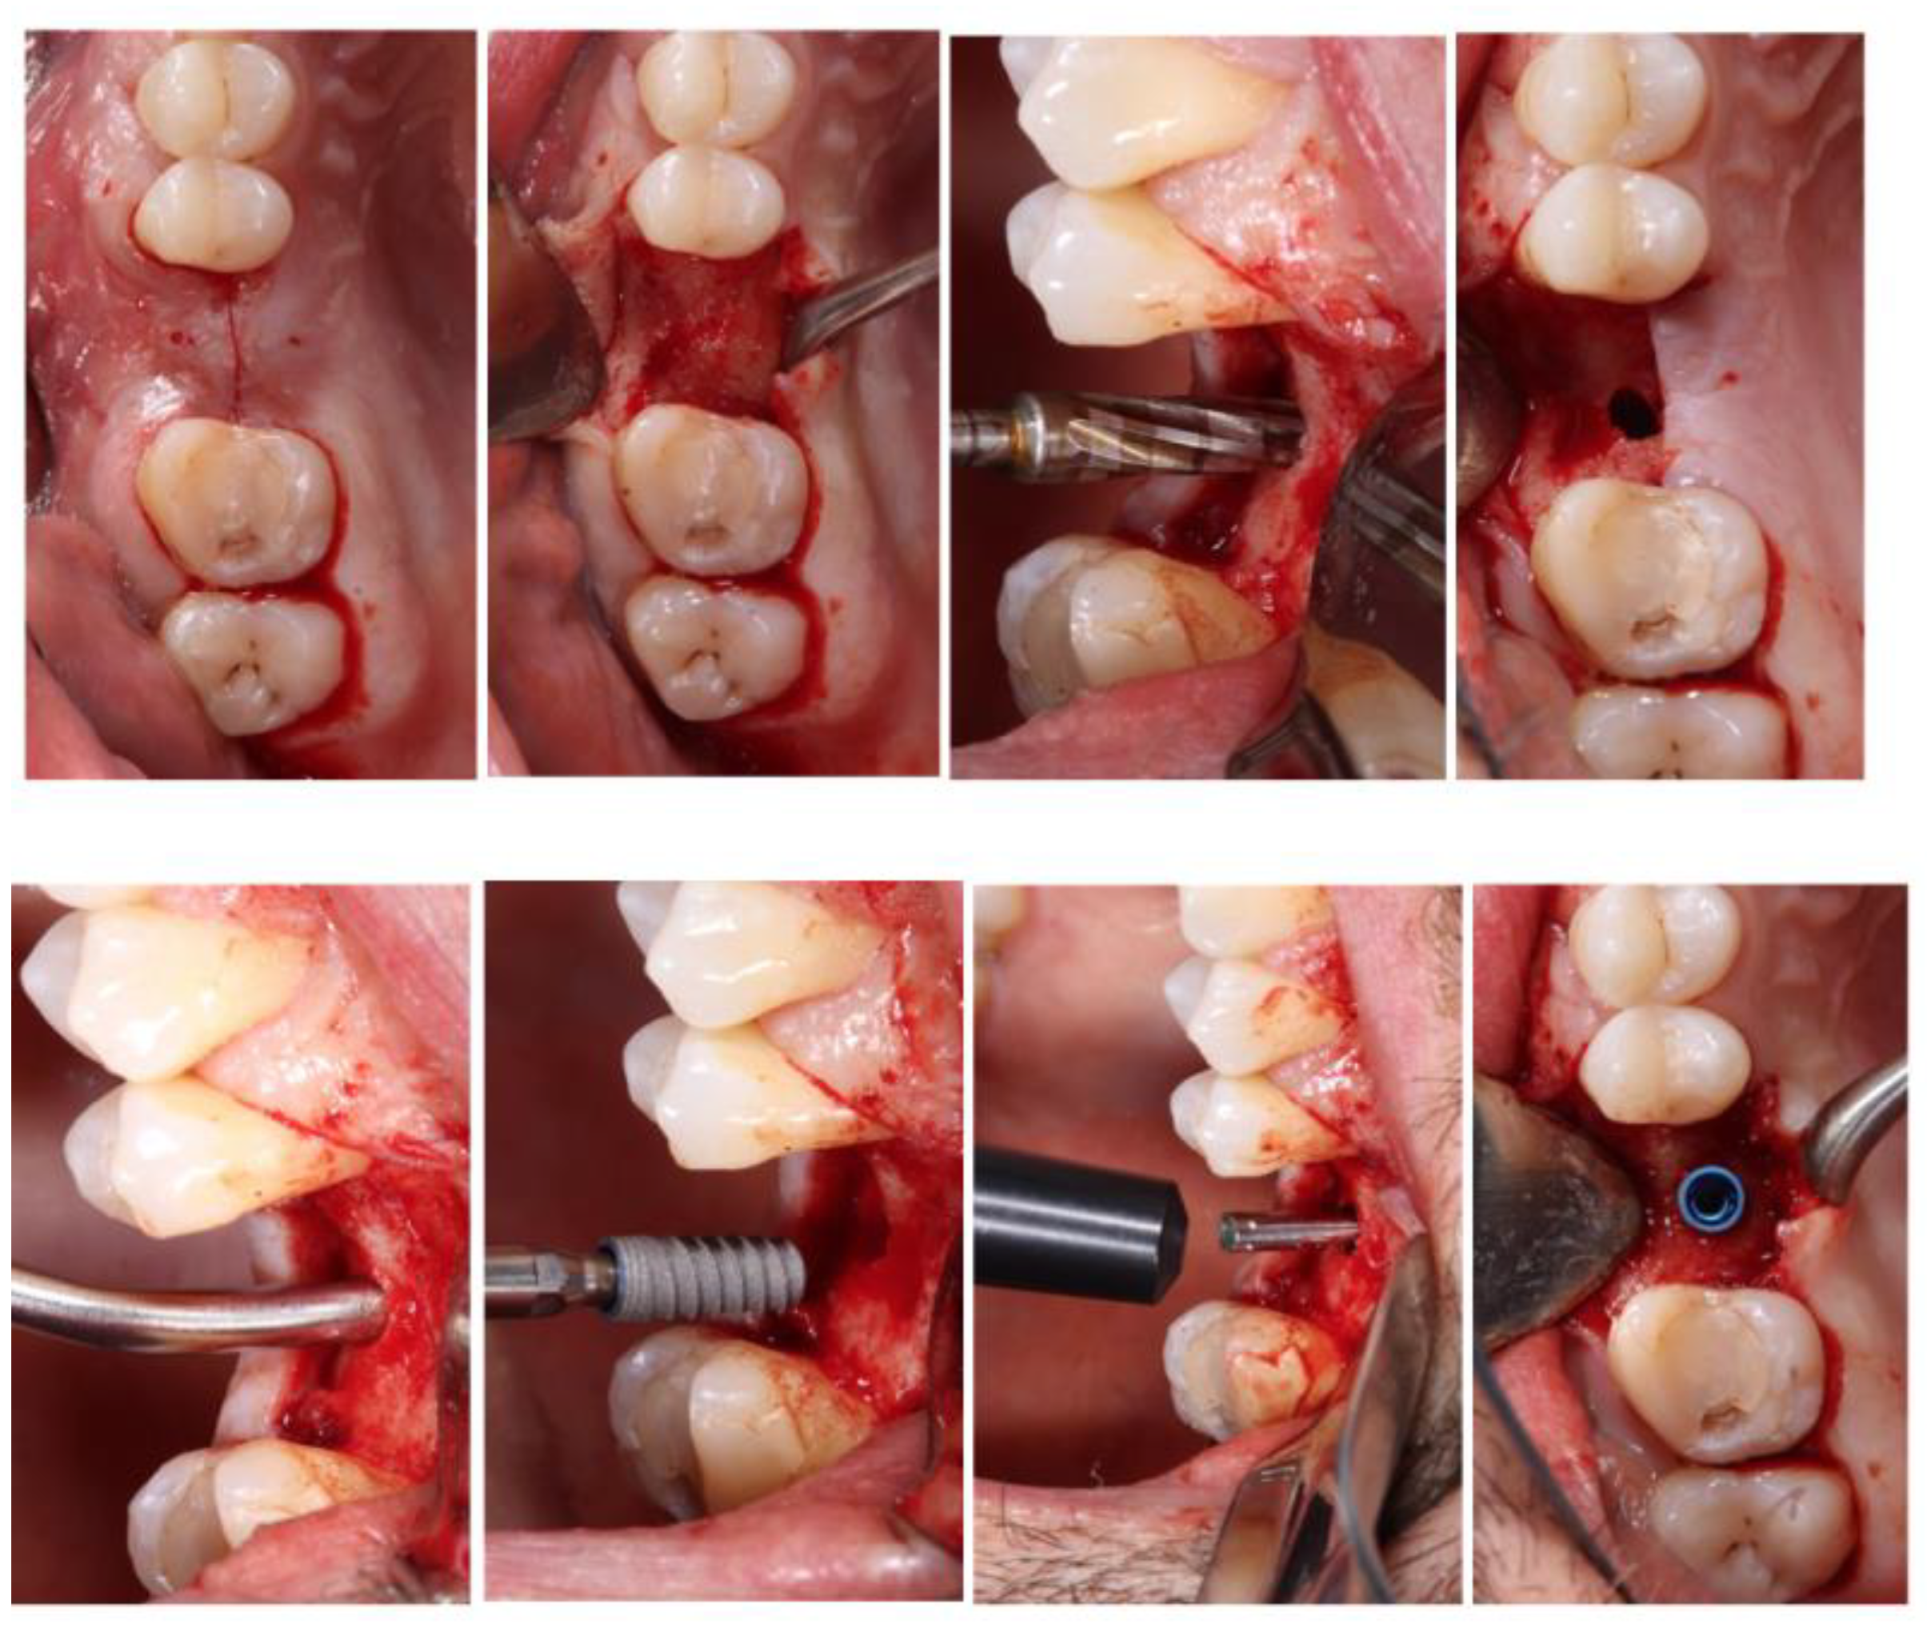

Surgical procedures were performed by second-year students of the Master of Oral Surgery and Implantology by five different clinicians, all of them with similar surgical experience, supervised by a professor expert in the OD and tSFE. After local anaesthesia (4% articaine with epinephrine 1:100.000), full-thickness flaps were reflected following a crestal incision and vertical releasing incisions if necessary. The preparation of the implant site/s was performed with Densah® burs by the Versah® system (Figure 1), which allows the compaction of the bone by small increments and a smooth expansion of the osteotomy, alternating between VT5 and VT8 (Figure 2) with abundant irrigation. Drills were rotated in a reversed, non-cutting direction allowing alveolar bone preservation and the increase in bone density.

Figure 3. Surgical procedure.

Preprints 101155 g003

The implant site preparation was started with a pilot drill to perforate the cortical bone, and a second drill (2.0) was used to define the orientation of the implant, to the depth of 1-1.5 mm away from the sinus floor. The final diameter of the osteotomy preparation had an average diameter of between 0.5-0.7 mm less than the diameter of the implant. As grafting material, beta-tricalcium phosphate (ß-TCP) NovaBone® was applied in the alveolar bed in gel format and compacted by the last drill used to break the sinus floor, rotated in a reversed direction, at 50 rpm and without irrigation. While compacting, for each grafting injection the drilled was inserted 1-1.5 mm deeper. An attempt to standardize the quantity of graft material placed into the sinus was made using one of the package contents (i.e. about 0.25-0.50 cc). All the implants were submerged and covered with soft tissue. All implants were left submerged and primary closure of the wound was obtained.